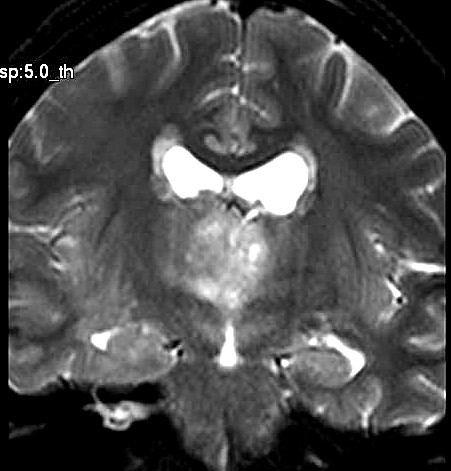

| Fem. 17a. |

| Nódulo sólido homogêneo preenchendo o III ventrículo, com limites precisos, com hipossinal em T1 e hipersinal em T2 e FLAIR, que se impregna por contraste paramagnético. Lesão menor implantada no assoalho do IV ventrículo provavelmente representa disseminação por via liquórica. |

| F. 17a. Tumor teratóide rabdóide atípico de III ventrículo. RM | HE | VIM, GFAP | HHF35, desmina, 1A4 | AE1AE3, EMA |